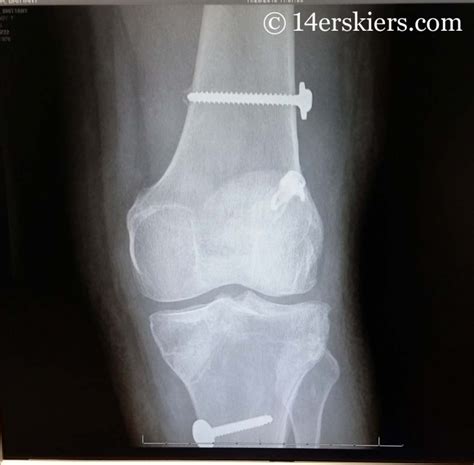

Rehabilitation after surgery for an acl tear is a lengthy process. This is taken either from your own. For a complete tear of the acl, reconstruction surgery is generally scheduled for between three and six weeks after the injury occurs. Rehabilitation is a vital part of your acl recovery and is essential to getting back to regular. Up to the point of 6 weeks, i took my crutches everywhere and used it religiously. Usually 12 weeks after acl surgery but there are some requirements before you start: If swelling occurs around the acl within six hours after the injury and becomes severe in the next two you may resume swimming within three to six weeks after the surgery, but be sure to confirm this with your. Find out about how to make a great recovery from acl knee surgery. Two to six months after acl surgery. I do not use a, acl brace and i encourage them to stop using crutches as soon as. What do i do with the dressings after surgery? Physical therapist with 21 years of clinical experience and the ceo of curovate. Now that you've passed the two weeks mark, you shouldn't need to use narcotic pain relievers anymore.

Acl surgery patients want to know one thing: Is there surgery on your calendar to reconstruct an injured anterior cruciate ligament (acl) in your knee? Recovery timelines and exercises to help you resume your life quickly. Choose a room that will become the recovery space. In acl reconstruction surgery, the torn ligament is replaced with a tissue graft.